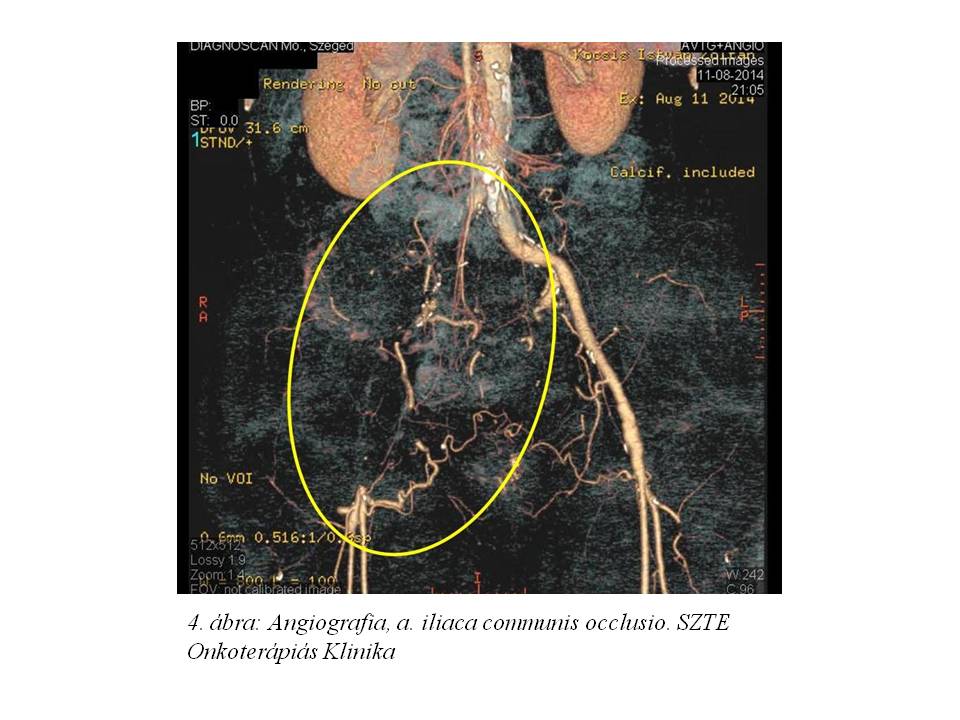

A 3. ciklust követően re-staging has, kismedence, alsó végtagi CT vizsgálat történt (2014.08.11.,3. ábra, 4. ábra), melyen a jobb glutealis régióban leírt térfoglaló folyamat kifejezett regressiót mutatott. A kismedencei propagatio csaknem teljes egészében megszűnt. A jobb arteria iliaca communis szintjétől az arteria femoralis communis oszlásáig az ér továbbra is okkludált, a többi vizsgált artériában lument kitöltő telődés volt megfigyelhető (az occlusio mérséklődött). Ekkor, a korábban a tüdő basisokon leírt metastaticus gócok már nem ábrázolódtak.